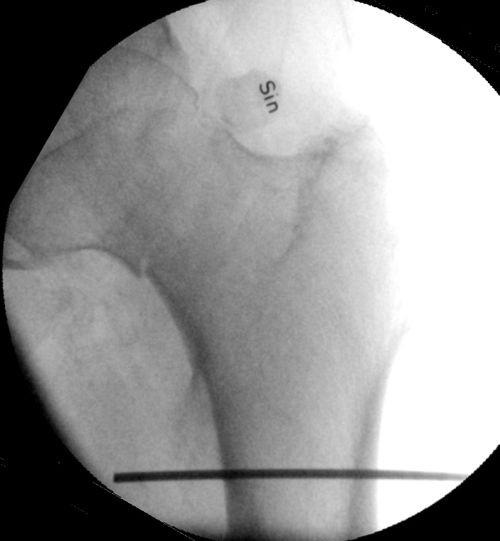

- Håll k-tråd tvärgående över femur i genomlysning på frontalbild, markera en linje längs med tuberkulum minors distala kant med en penna eller genom att dra k-tråden mot underlaget.

- Håll k-tråd parallellt med femur i genomlysning på sidobild, alternativt palpera femur, markera en linje horisontellt, strax dorsalt om centrum i femur. OBS! Inte ventralt om centrum, då blir det svårt att sätta pinnarna rätt!

K-tråd hålls längs femur på sidobild. Markera längsgående linje ca 1 cm dorsalt om denna.